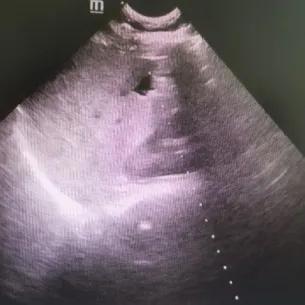

经过充分的术前评估,完善的术前相关检查,手术在实时超声引导监测下进行,动态观察穿刺针的位置,精确穿刺、精确抽吸,共抽出液体162ml,然后注入3ml利多卡因,停留3分钟后抽出,而后注入13ml无水乙醇,停留5分钟后抽出13ml液体,超声监测囊肿消失。整个手术过程病人处于完全清醒状态下,手术过程近1小时,术后留观1小时,患者无明显出血及不良反应后,在家属陪同下出院。(附肝囊肿硬化治疗前后超声图对比,图1、图2)

图2:硬化治疗后